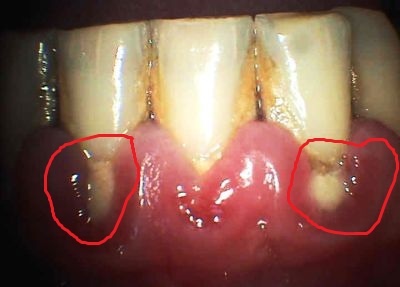

kaz, znt - v ervenm krouku

Na obrázku - zubní kámen, zánět dásně, ústup dásně a v oblasti krčku zubu nejspíš kaz. Špatná hygiena. Z obrázku je to jak vařit z vody....

Parodontóza tam může být taky, ale k tomu je potřeba konkrétní vyšetření.

Tak takhle vypadá ústup dásně a odhalení krčku, dále vidím zubní kámen a docela silný zánět dásní-takže terapie je odstranění zubního kamene, důsledná domácí hygiena, včetně čištění mezizubních prostorů, kombinovaná s antibakteriálním výplachem(nejlépe chlorhexidin po dobu jednoho měsíce a následně pokračovat listerinem) a vyšetření na parodontologii, kde můžou zasáhnout i chirurgicky.